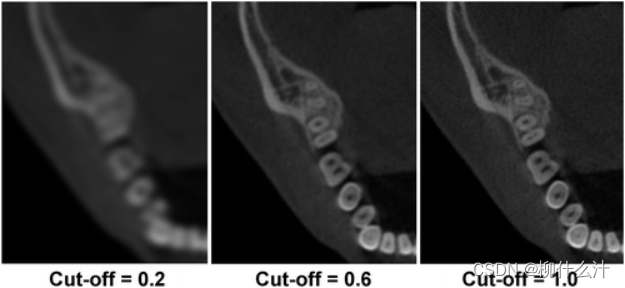

CBCT中使用的最广泛的三维FBP形式是Feldkamp-Davis-Kress(FDK)算法,由于其简单和快速的重建时间,几乎所有的CBCT机器都使用这种算法。投影数据是沿射线路径的线性衰减系数的总和,可称为正向投影,而FBP(和FDK算法)基本上是加权和过滤投影的逆向或背向投影过程,其中投影图像中每个像素的值被分配给沿X射线路径的每个体素(图10)。当对每一个投影进行这样的处理时,就可以重建一个扫描物体的图像。滤波器由两部分组成:(1)一个斜坡滤波器,以纠正投影/背投过程中固有的模糊现象;(2)一个平滑滤波器,以减少被斜坡滤波器放大的高频噪声。这种平滑滤波器是可选的,并可根据其截止频率进行调整,该频率可表示为奈奎斯特频率(即图像中最高的可显示频率)的一个分数。平滑滤波器可以通过以空间分辨率为代价减少噪声来显著影响图像质量。从最清晰到最平滑的重建滤波器的例子包括Ram-Lak(一个纯斜坡滤波器)、Shepp-Logan、Cosine、Hamming和Hann。这类滤波器的截止频率可以自由调节:截止频率越高,重建的图像越清晰,但噪音越大。一些软件可能允许用户根据特定成像任务的需要调整重建参数。

CBCT图像显示了使用余弦重建滤波器的不同截止频率(以Nyquist频率的一部分表示)的效果。较大的截止频率会增加空间分辨率和噪声